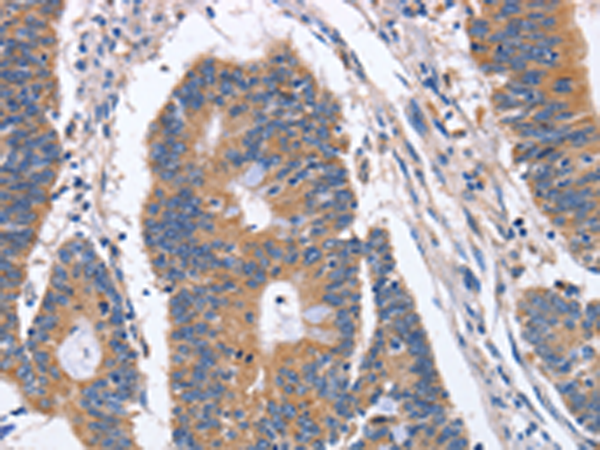

分类: 科研抗体货号: P11621别名: CAPZ; CAZ1; CAPPA1应用: IHC反应种属: Human, Mouse, Rat